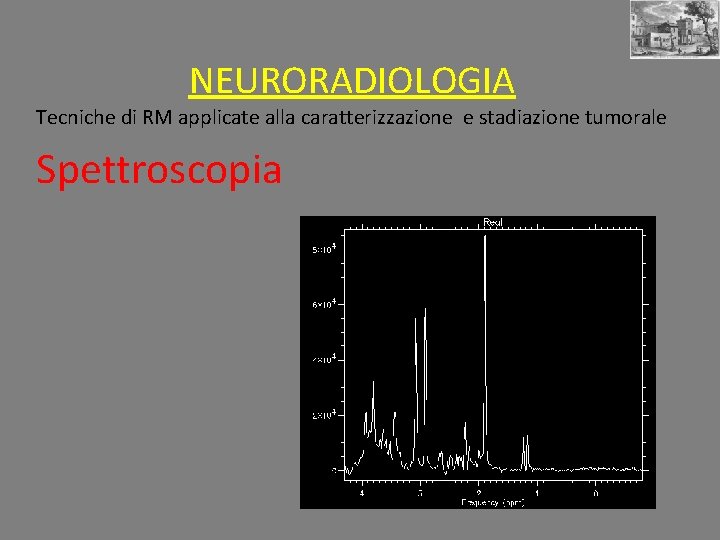

NEURORADIOLOGIA Tecniche di RM applicate alla caratterizzazione e stadiazione tumorale Spettroscopia Tecnica non invasiva che valuta il profilo metabolico (quantitativo e qualitativo) del tessuto preso in esame mediante particolari sequenze di risonanza magnetica METABOLITI PRESI IN ESAME : N-Acetilaspartato (Naa da 1. 9 a 2. 1 ppm) marker di integrita’ neuronale Colina (Cho da 3. 1 a 3. 3 ppm) marker di proliferazione cellulare e di turnover di membrana Creatina (Cr da 2. 9 a 3. 1 ppm) marker di metabolismo energetico Lattati (Lac da 1. 3 a 1. 5 ppm) marker di ipossia tissutale Lipidi (Lip da 0 a 1. 9 ppm) marker di necrosi tissutale Myo-Inositolo (Myo-Ino 3. 5 ppm) marker gliale Glutammato e Glutammina (Glx da 2. 05 a 2. 5 ppm) marker di eccitotossicità

NEURORADIOLOGIA Tecniche di RM applicate alla caratterizzazione e stadiazione tumorale Spettroscopia